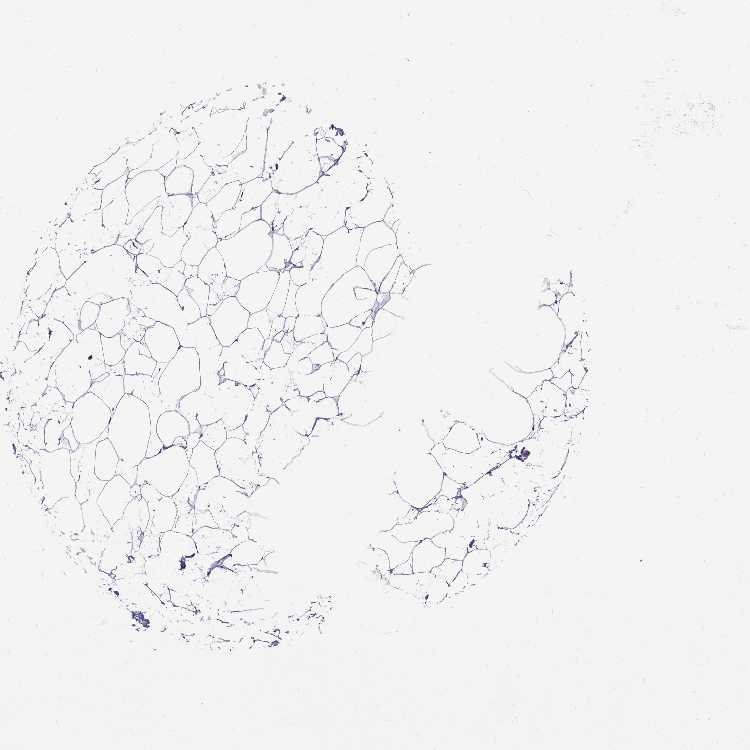

ADIPOSE TISSUE - Antibody stainingi

Antibody staining in the annotated cell types in the current human tissue is reported as not detected, low, medium, or high, based on conventional immunohistochemistry profiling in selected tissues. This score is based on the combination of the staining intensity and fraction of stained cells.

Each image is clickable and will lead to virtual microscopy that enables deeper exploration of all samples and also displays staining intensity scores, fraction scores and subcellular localization as well as patient and tissue information for each sample.

Antibody HPA044404Antibody HPA052908

Adipocytes Not detectedNot detected